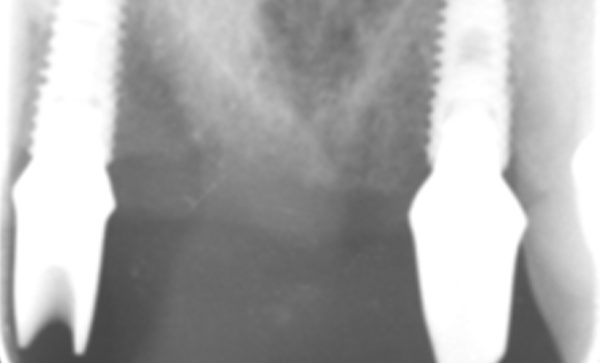

Case 9